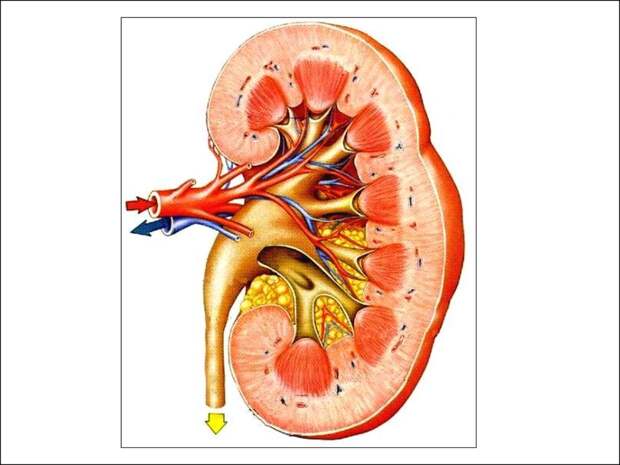

Нефрит — воспаление почек. Существует несколько форм нефрита.Острый нефрит. Это заболевание развивается как осложнение заболеваний верхних дыхательных путей, воспаления легких, тифа. Симптомами острого нефрита являются: повышение артериального давления, отеки.

Хронический нефрит. При этом заболевании время от времени появляются обострения с симптомами и признаками острого нефрита.